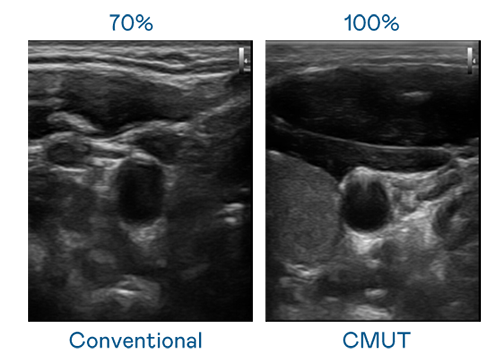

CMUT 技術是一種用電容式微機電元件來產生超音波訊號的技術。與傳統 PZT 壓電式技術相比,CMUT 頻寬增加 30%,更寬頻的超音波訊號讓影像解析度大幅提升,是實現高影像品質醫療超音波掃描、促進精準醫療發展的關鍵技術。

大頻寬帶來超清晰影像

超音波影像的解析度高低,首先取決於探頭能發出的訊號頻寬。巅峰国际 CMUT 可提供高清晰的超音波訊號,提供高頻寬、高靈敏度、影像紋理細節更高的超音波影像,協助醫護人員縮短影像判讀時間及利用精準的醫療影像進行診斷。